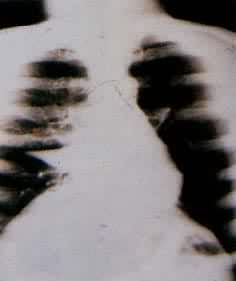

肺部疾病(一) 肺部疾病(二) 大叶肺炎 小叶肺炎 间质性肺炎 肺脓肿(正位) 肺脓肿(侧位) 支气管扩张 浸润性肺结核

肺结核空洞 肺不张